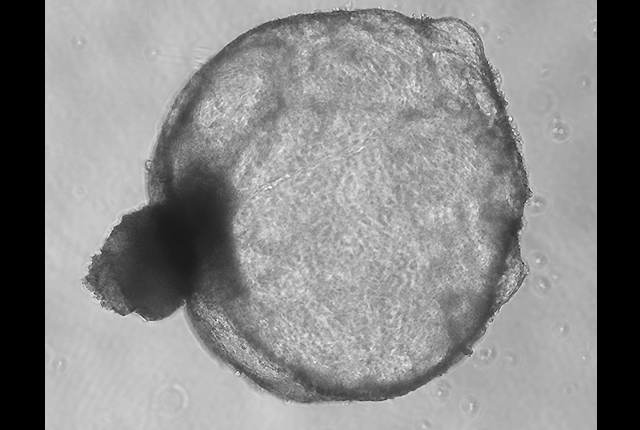

Dr. Pavan Bhatraju, a KRI investigator, Dr. Daniel T. Chiu, a MolES investigator, and Dr. Ying Zheng, who is affiliated with both institutes, earned a pilot project award of $10,000 for the project "Screening Biomarkers for Human Kidney Microvascular Endothelial Injury in Cytokine Storm." They actively participated in the MolES/KRI Scientific Exchange Meetings during Spring 2024.